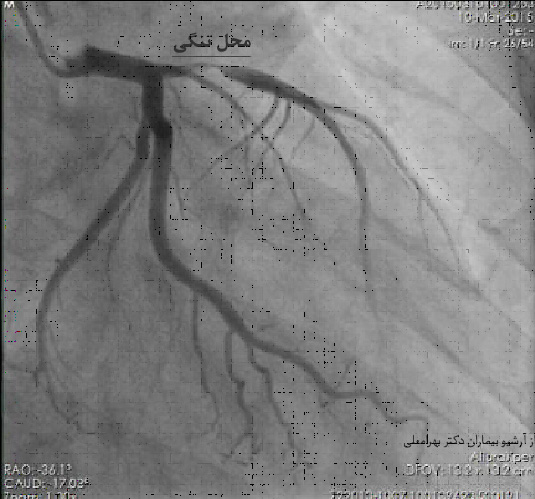

آنژیوگرافی عروق کرونر (انجیو) روشی است که متخصّصان قلب به عنوان استاندارد تشخیص گرفتگی عروق قلبی به کار می برند. (روش انجام آنژیوگرافی عروق کرونر) تصاویر به دست آمده در آنژیوگرافی(angiography) محل و شدّت تنگی رگ یا رگها را نشان می دهد و چنانچه مقدور باشد فوق تخصص آنژیوپلاستیangioplasty (آنژیوپلاستی چیست) می تواند در همان حال برای باز کردن تنگی اقدام کند.